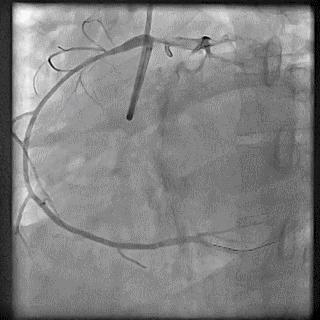

(4)LIMA桥血管造影

首选导管:JR4.0导管

其他导管:如果开口明显成角应选用专用的内乳动脉造影导管

➢ CASE 6

经股动脉途径TIG,非选择造影如果能清晰显影,可不做超选造影

➢ CASE 7

经左侧桡动脉途径JR4.0,非选择造影如果能清晰显影,可不做超选造影